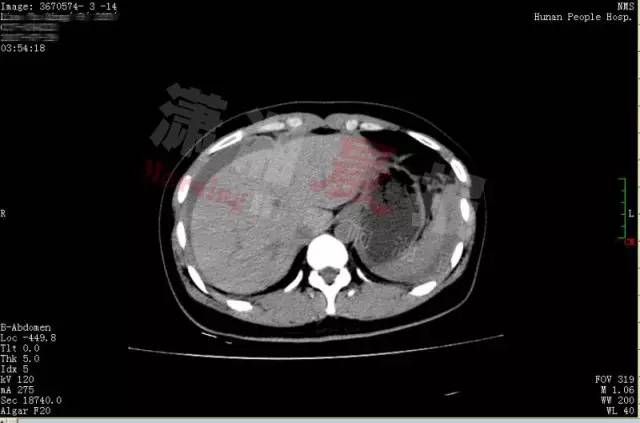

谁知激情过后,小晴出现下腹部疼痛,而且越痛越厉害,只得来到湖南省人民医院天兴阁院区急诊科就诊。尿妊娩检查结果为阴性,而腹部 CT 提示盆腔、腹腔有大量积血、积液,随即转入妇科。

黄主任立即为小晴进行诊断性腹腔镜手术,术中发现腹腔内积血约 1500ml,接近她全身总血量的 40%," 再晚一点来,就会危及生命了 "。医生还发现,在她右侧卵巢有一个直径 3cm 左右的黄体囊肿表面有破口,破口有血块附着,还有活动性出血。黄薇立即为她施行黄体囊肿剥除和创面缝合止血手术,恢复了卵巢的正常形态。